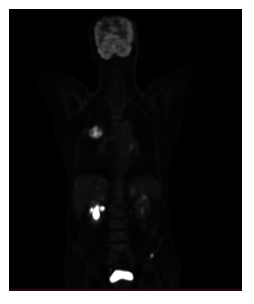

A 70-year-old male patient visited the outpatient clinic with a past medical record of diabetes type II, arterial hypertension under treatment and a history of three months with fatigue, nonproductive cough and dyspnea. During the clinical examination the patient was found to be afebrile and presented on auscultation with respiratory wheezing and presence of abundant crackles in the left hemithorax. The patient’s blood test showed mild anemia with a hemoglobin level 10.9g/dl, the white blood cell count was slightly elevated at 11.8 × 10³/µL due to an increase on neutrophils. Tumor markers showed a CEA (carcinoembryonic antigen) level of 88 U/mL, which is higher than normal. Additional imaging was performed with a chest computed tomography, which revealed a right upper lung solid mass measuring 51x44mm, accompanied with carcinomatous lymphangitis. The patent underwent an 18F-FDG PET/CT scan to assess the extent of the disease. In addition to the pulmonary lesion and carcinomatous lymphangitis, bone lesions were also identified. There were two lesions, one in the right humeral diaphysis, with high radiotracer uptake, (SUV max 8.8), and another in the left iliac bone with similar characteristics (SUV max 14.2). These lesions are PET positive, but not visible on computed tomography, suggesting early bone metastases.

Our patient was a 65-year-old female diagnosed with Grade III ER-/PR-/Her-2 invasive ductal carcinoma in the left breast. She underwent neoadjuvant chemotherapy, followed by left mastectomy and radiotherapy. Six months after completion of therapy, the patient presented for a routine clinical evaluation and underwent a follow-up 18F-FDG PET/CT examination. At the time of referral, the patient reported mild persistent pain in the right upper limb, without a history of trauma. The laboratory tests showed normal platelet counts, hemoglobine and white blood cells, mild elevation of alkaline phosphatase. In addition, tumor marker CA 15-3 was above the normal refrence range 68U/mL, while CEA was normal. Liver and renal function test were within the normal limits. The 18F-FDG PET/CT images identified two focal areas of increased radiotracer uptake in the right iliac bone and the right femoral bone, both without noticable structural abnormalities on the CT. There were considered metabolically active but CT-negative bone lesions. Furthermore, a focal FDG-avid pulmonary lesion was detected, suspicious for lung metastases.